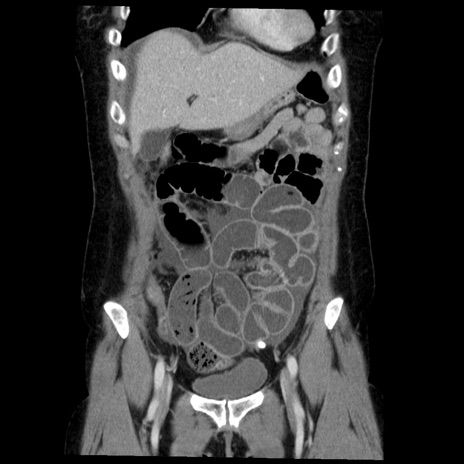

症例6(冠状断像)

【症例】50歳代女性

【主訴】下腹部痛

【現病歴】本日朝より下痢2回あり。 昼食を食べた後、嘔吐3回、下腹部痛認め、症状軽快せず、当院救急搬送。

最終食事:本日昼(生ものなし)。 昨日の夜、刺身を食ぺたとのこと。周囲に同様の症状の者なし。普段、排便は毎日あるとのこと。

【既往歴】卵巣癌術後(8年前に当院で卵巣摘出)

【身体所見】 意識清明、腹部:平坦、腸蠕動音→、やや硬、下腹部自発痛・圧痛あり、反跳痛あり、筋性防御なし。

【データ】WBC 16000、CRP 0.01